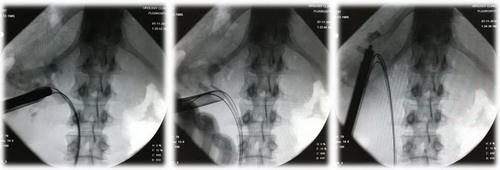

Рис. Рентгенологические этапы операции.

Реальный кейс: чрескожная нефролитотрипсия пациентке 28 лет при коралловидном камне

Операция: Чрескожная нефролитотрипсия.

Хирург: доктор медицинских наук Акопян Г.Н.